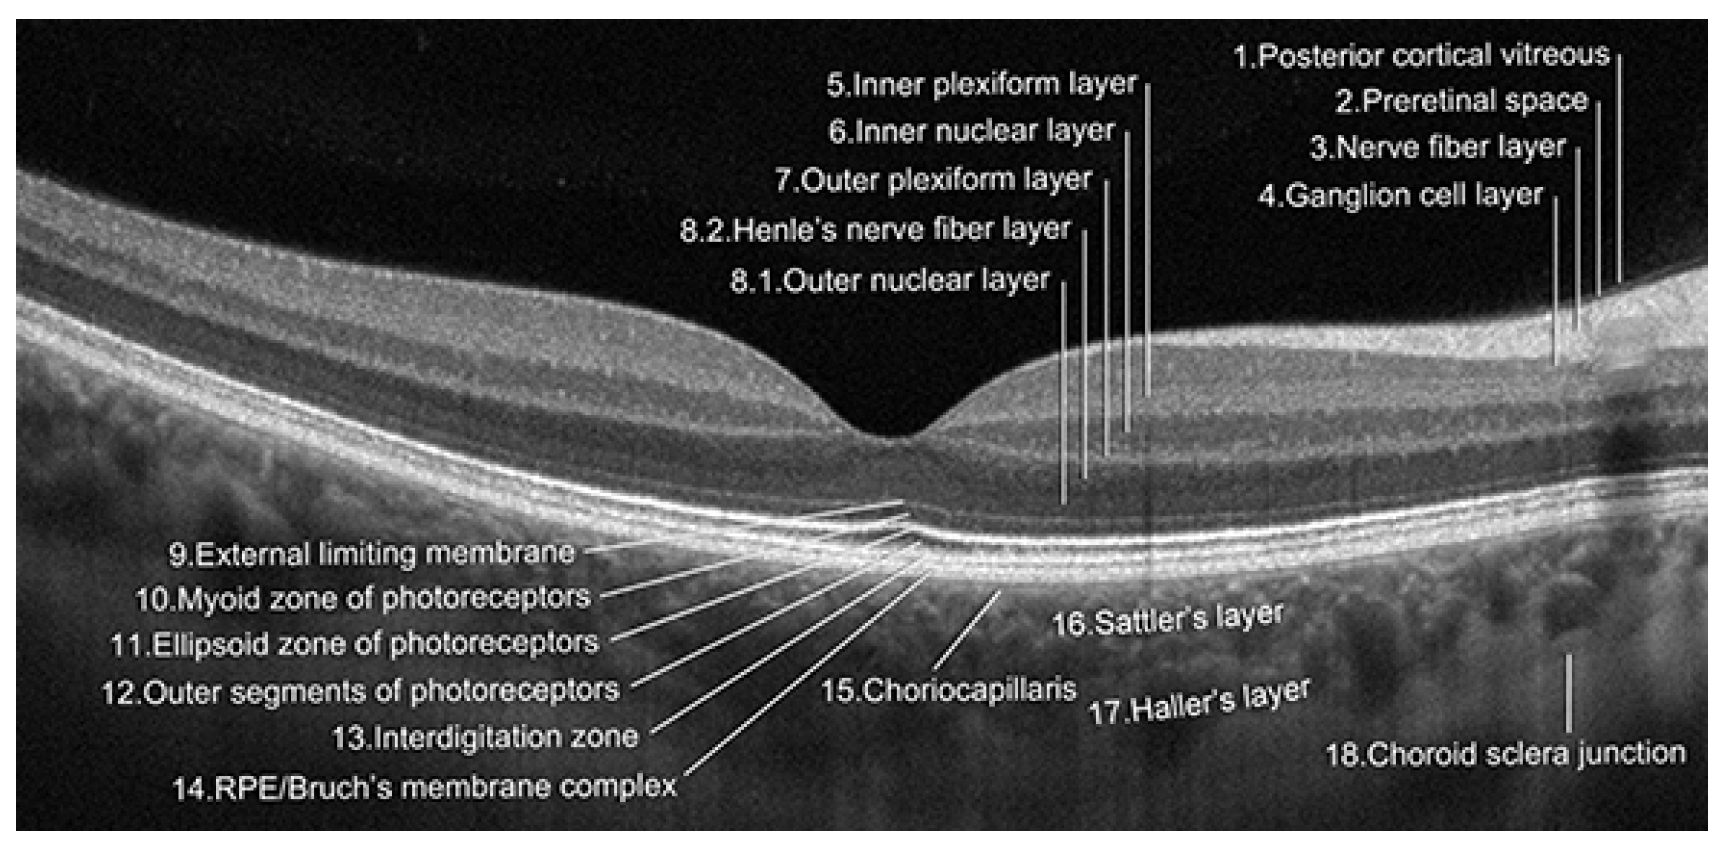

:1. Introduction

3. Treatment of Neovascular AMD